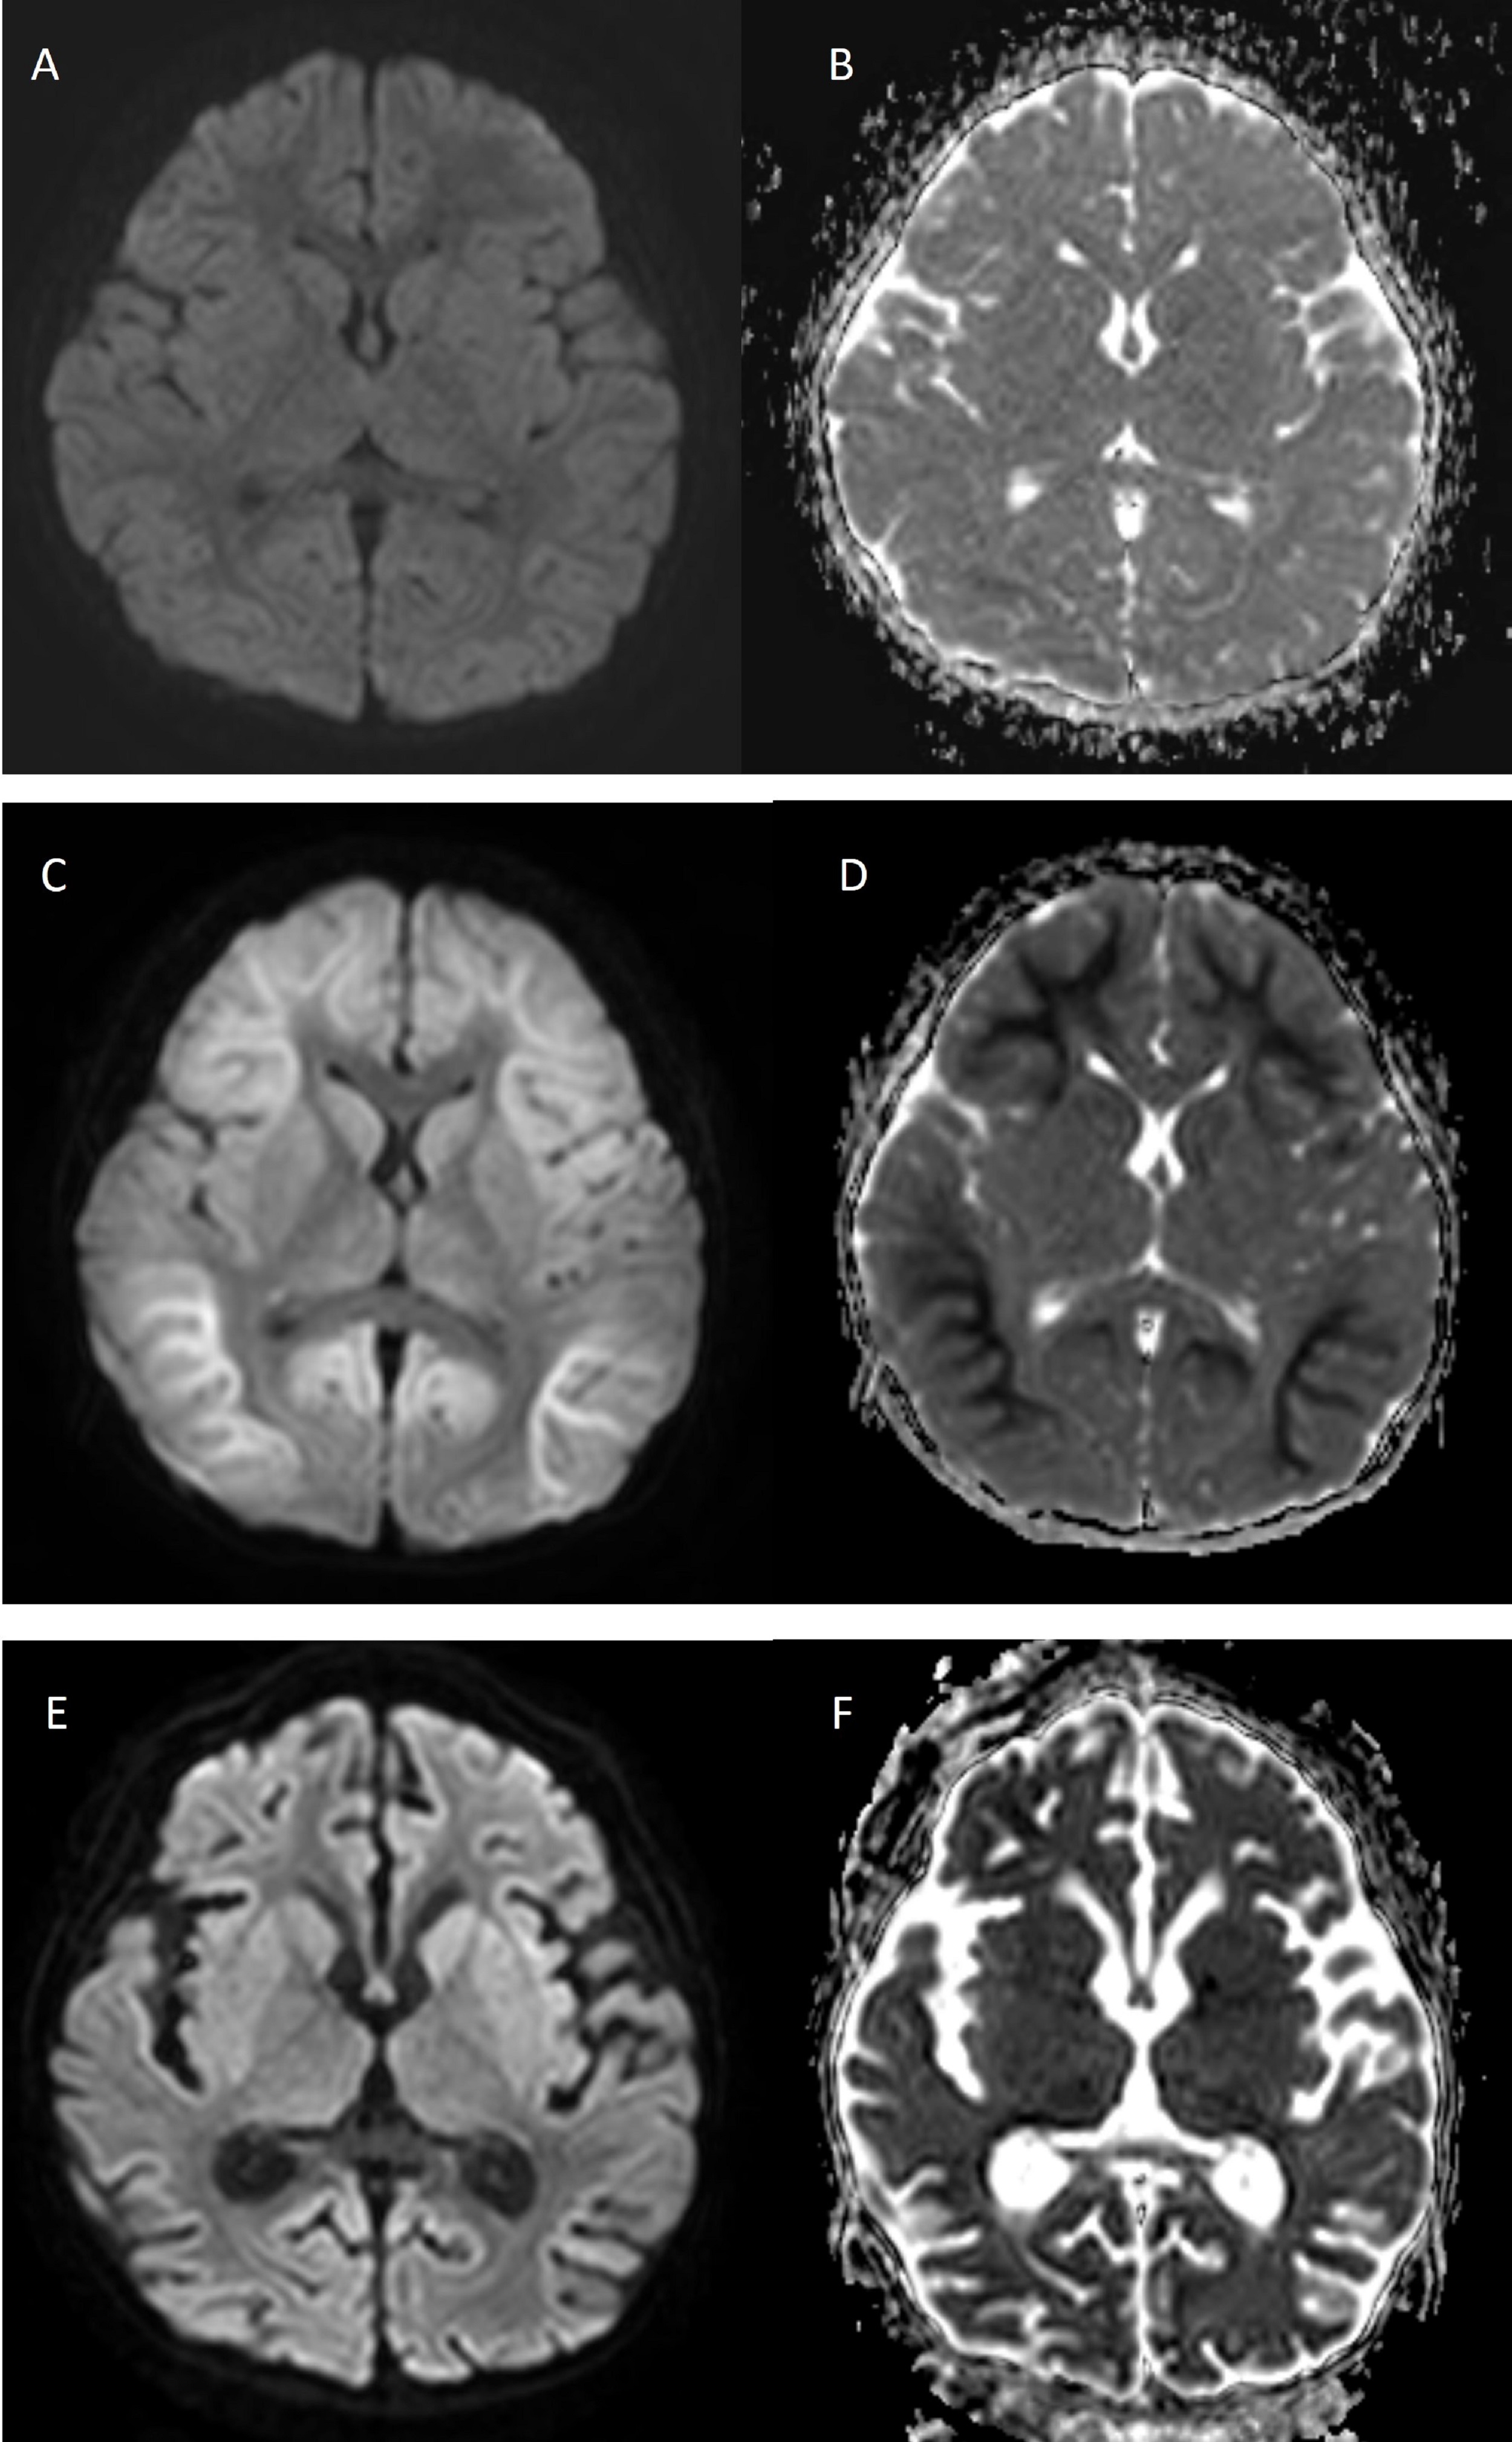

Rationale: Acute encephalopathy with biphasic seizures and late reduced diffusion (AESD) is a subtype of acute encephalopathy described in a cohort of Japanese children. It is characterized clinically by biphasic seizures and late reduced subcortical diffusion on magnetic resonance imaging (MRI). Reports of AESD involving other ethnic groups are rare, as are those with a preceding adenovirus infection. We report the first Korean case of AESD in association with preceding adenoviral infection. Methods: We present clinical, electroencephalographic and radiologic features of our rare case. Results: A previously healthy 3-year-old Korean girl presented with statue epilepticus that started with focal impaired awareness with upward eye deviation following a 5-day prodromal illness consisting of fever, cough, sputum production, and rhinorrhea. Her seizures were refractory to typical doses of benzodiazepines but were subsequently controlled with a bolus of intravenous phenobarbital. Her chest radiograph showed pneumonic consolidation of the right lower lung field. Blood, urine, and CSF cultures showed no growth, and CSF polymerase chain reaction (PCR) for enterovirus, herpes simplex virus type 1 and 2, varicella zoster virus, cytomegalovirus, measles, HHV-6, and adenovirus was negative. However, multiplex real-time reverse transcriptase PCR assay for respiratory viruses from a nasopharyngeal aspirate was positive for human adenovirus. Initial brain MRI with diffusion-weighted imaging (DWI) and electroencephalography (EEG) showed no abnormality on day 3 of hospitalization (Figure 1A & 1B). After 5 days, she developed a second cluster of seizures followed by altered consciousness, aphasia, stereotypic movement, and developmental regression. Her seizure was controlled with levetiracetam. Her brain MRI showed symmetrical and extensive restricted diffusion in the subcortical white matter, which finally resulted in global brain atrophy, consistent with AESD (Figures 1C & 1D). Approximately 1 month later, she regained her gross motor functions. However, her brain MRI showed diffused atrophic changes involving both cerebral hemispheres (Figure 1E & 1F). One year later, she still showed psychomotor developmental regression and focal epilepsy, with diffused parenchymal atrophy without any interval change on brain MRI. Conclusions: We report what is, to our knowledge, the first case of a Korean child presenting with AESD preceded by adenoviral pneumonia. However, many cases with AESD might be missed because MRI abnormality is not seen for a few days. The diagnosis of AESD is based on the presence of biphasic seizures, and distinctive imaging features. Brain MRI with DWI is an essential tool to detect this type of encephalopathy in a patient with febrile status epilepticus who is showing repetitive seizures or neurologic deterioration. Therefore, pediatric neurologists should be aware of the clinicoradiologic features of acute encephalopathy and perform brain MRI aggressively in patients suspected of having AESD, to detect the dynamic MRI changes. Funding: None